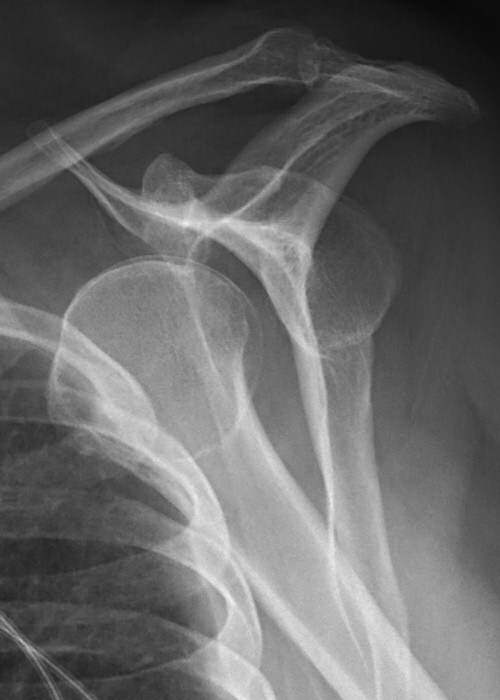

Främre luxation